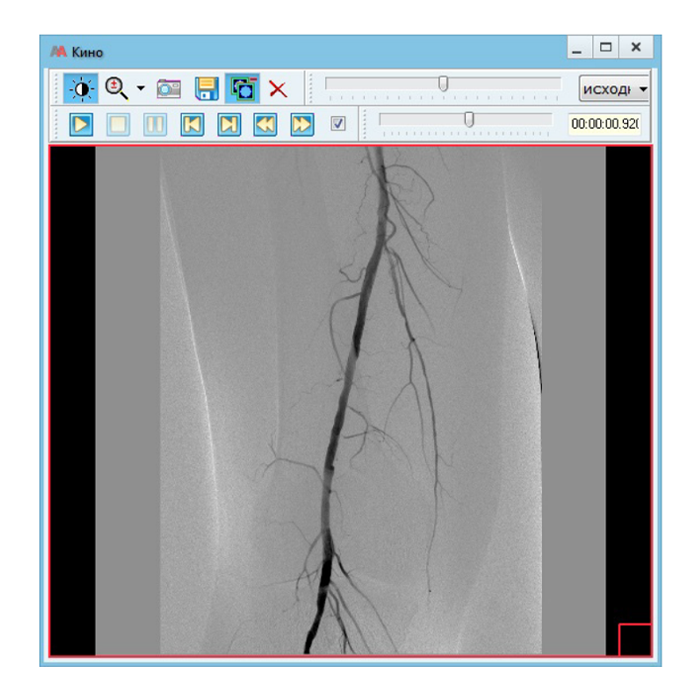

- Работа с изображениями: Автоматический прием снимков с любого DICOM-совместимого оборудования (КТ, МРТ, рентген, УЗИ и др.), организация единого защищенного архива.

| Поддерживаемые модальности | КТ, МРТ, рентген (в т.ч. цифровой), маммография, УЗИ, ангиография и другие DICOM-совместимые аппараты |

- Повышение качества диагностики: Доступ к полной истории изображений пациента, инструменты для сравнения, точных измерений и постобработки.